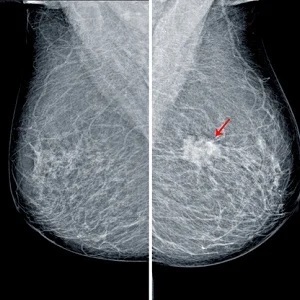

The workforce supply in Canada, although increasing, has not matched the demand for breast radiologists. To gauge the interest level for breast imaging and determine factors influencing radiology trainees’ decision to pursue this subspeciality, Canadian researchers sent a survey to all 16 radiology programs and all 17 medical schools’ radiology interest groups. They examined survey responses from Canadian residents in postgraduate years 1-5 and all medical students from years 1-4. Survey respondents included 80 residents along with 77 more medical students.

They found that performing procedures under sonographic, mammographic, or MRI guidance are desirable features of breast imaging, whereas its perceived repetitiveness is not. About 20.4% of respondents expected breast imaging to be repetitive. Radiology residents were also deterred by the high workload (6%) and fear of lawsuits (15%), while these factors bothered medical students less (0% and 5% of medical school respondents, respectively). About 59% of respondents found the associated procedures appealing, a factor associated with interest in breast imaging fellowships. The subspeciality's patient-facing nature was considered a prime motivator.

Canadian researchers found that performing procedures under sonographic, mammographic, or MRI guidance are desirable features of breast imaging, whereas its perceived repetitiveness is not.